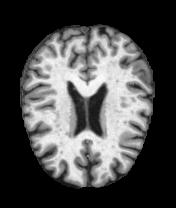

MRI Brain Scans Dataset - All Categories

Normal Cognition

Healthy brain structure

Real MRI scans showing progressive structural brain changes across all dementia stages

- • Total Images: 6,400+ brain scans

- • Normal Cognition: 3,200 cases

- • Very Mild Dementia: 2,240 cases

- • Mild Dementia: 896 cases

- • Moderate Dementia: 64 cases